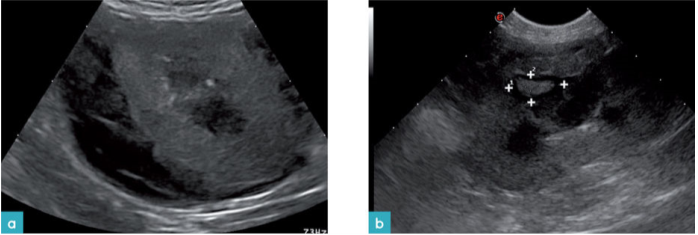

软组织积聚(有时被钙化),具有肾盂肾炎或固化血液的炎症物质是导致输尿管梗阻的其他原因。在超声上,钙化和尿结石表现为具有声学阴影的强回声结构。这种声学阴影可以被标记:然而有时,特别是如果结石非常小,那么阴影可能非常微小或几乎不存在。尿结石与钙化存在区别,因为结石通常被液体包围且倾向于产生肾盂或输尿管的扩张(图32和33.视频14和17)。如使用彩色多普勒超声时观察到闪烁伪象,那么其有助于确定钙化和结石的存在(图34.视频18)。

在一些情况下,输尿管壁增厚和肠脂肪周围的回声反应性增加存在相关性(图35)。输尿管梗阻的一种治疗方法是放置皮下输尿管旁路装置或输尿管支架(图36)。